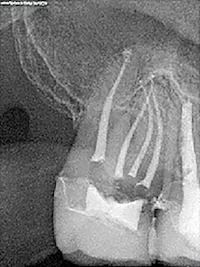

TP 11 - Endodontie : Préparation canalaire – système Race (FKG) - et obturation simplifiée

par Bertrand Khayat

Acquérir un geste rapide, précis et léger avec le système Race (FKG)

Discipline abordée : Endodontie.

La combinaison des instruments FKG Scout Race et de la séquence iRace offre une solution globale en rotation continue plus rapide et plus sûre dans la préparation canalaire » explique Bertrand Khayat, responsable de ce TP.

Et d’ajouter : « l’introduction d’un nouvel instrument rotatif à mémoire de forme permet un meilleur nettoyage sans élargissement du canal afin de préserver la résistance de la dent. »

Destiné aux omnipraticiens, ce TP vise à se familiariser avec le système Race, impliquant une technique récente et encore peu répandue mais qui présente de nombreux avantages. En effet, cet instrument permet de s’affranchir complètement de l’instrumentation manuelle, en particulier dans la phase initiale du traitement. Le cathétérisme est alors réalisé de manière mécanisée avec des instruments rotatifs très particuliers qu’il faut savoir maîtriser.

Concrètement, dans un premier temps, une phase théorique concise et pratique présentera le système Race avant une démonstration sur un bloc en plastique. Encadrés par l’équipe pédagogique, les participants réaliseront ensuite des préparations canalaires avec le système Race sur des blocs en plastique et des dents naturelles extraites qu’ils auront spécifiquement apportées pour le TP.

L’après-midi, ils obtureront les dents préalablement préparées. Deux techniques d’obturation seront proposées : la technique de condensation thermomécanique et la technique mono-cône biocéramique.

L’objectif : maîtriser ces deux techniques afin d’élargir le panel de choix du praticien.

L’accent sera mis tout au long de la séance sur la dynamique instrumentale spécifique de l’instrument Race qui nécessite un geste rapide, précis et léger.

Responsable scientifique : Bertrand Khayat.

Equipe pédagogique : Cauris Couvrechel, Julien Dusart, Guillaume Jouany.

Les objectifs de la formation :

- Se familiariser avec le système Race.

- Comprendre la dynamique spécifique de l’instrument.

- Mettre les deux techniques d’obturations proposées en rapport avec cette technique de préparation